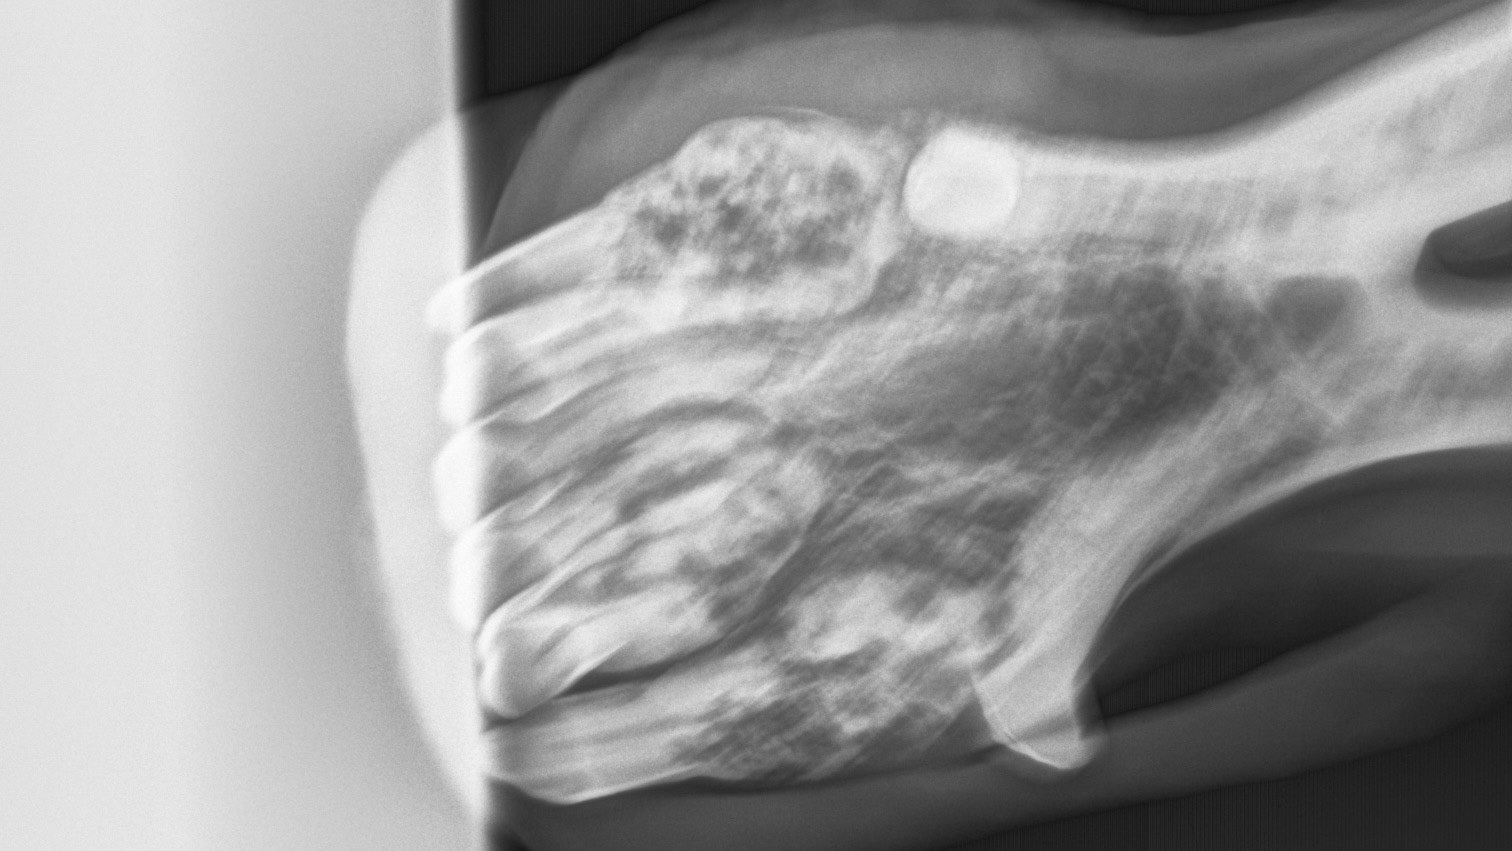

A radiograph (X-ray) of the canines and incisor teeth in a horse with EOTRH. Note the lacy look of the bone where the teeth insert as well as the enlargement of the tooth roots as they struggle to hang on.